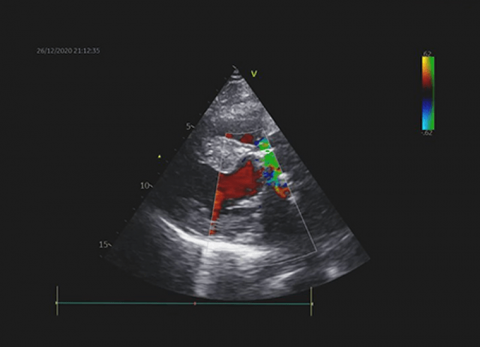

Wideo Echokardiografia. Przypadek 7

prof. dr hab. n. med. Piotr LipiecPacjentka z pogorszeniem tolerancji wysiłku, kołataniami serca i cichym szmerem skurczowym.